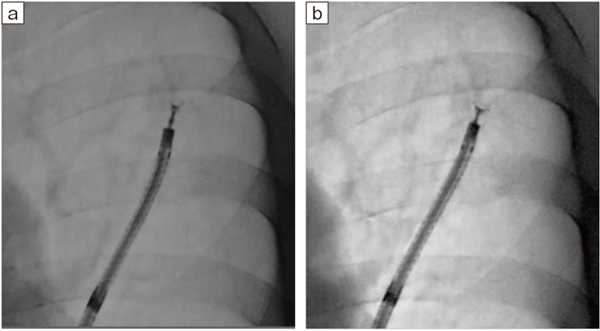

図10 パルス透視の各フレームレートにおける病変とデバイスの視認性

a:3.75fps b:7.5fps c:15fps

低線量の低いフレームレートでも、病変の位置確認やガイドシース先端の観察に十分な画像が得られている(Accent適用症例画像)。

(ガイドシース:GuideSheathKit2、オリンパス社製)